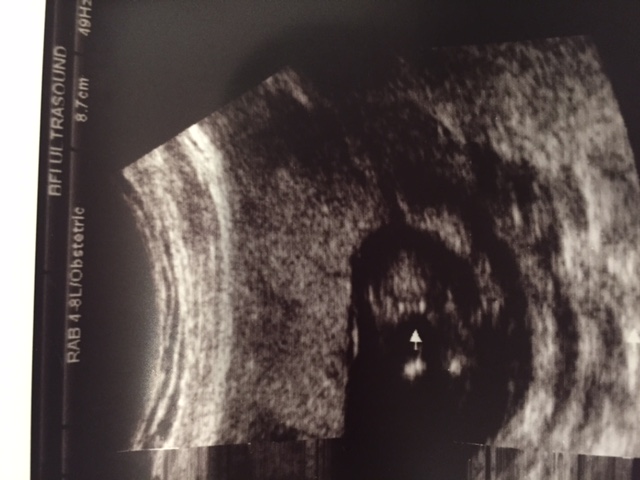

Ok so I had my 13 weeks ultrasound today and the technician said she was 99.9% it is a... I won't tell just yet because I would love to hear your opinion. I'm so happy that I can't believe this is actually happening and I'm afraid that my 20 week scan will show something different!!! Here are the pictures:

Attachment 24291